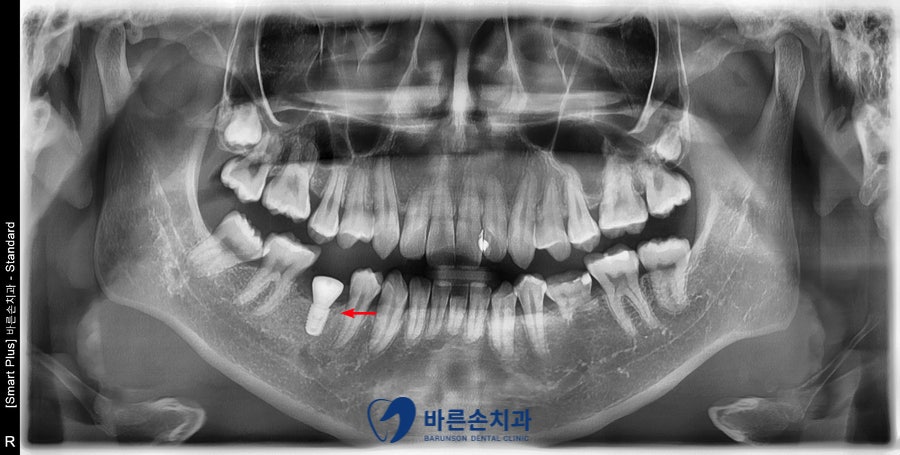

임플란트를 식립 하였습니다.

CT를 찍어 임플란트가 잘 심어졌는지

확인 후 수술을 마무리 하였습니다.

이제 임플란트와 뼈가 굳는 기간인 약 3개월정도를 기다린 후

임플란트 보철을 만들어 드릴 예정입니다. ^^